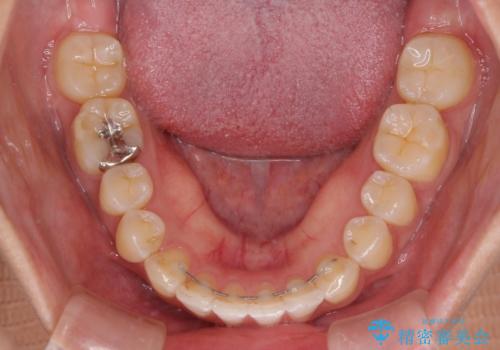

口元の突出感はインビザラインにより歯列を整え、その後に、前歯をオーダーメイドタイプのオールセラミッククラウンにて補綴治療することとしました。

長時間のマウスピース装着と、患者様自身でのゴムかけに協力いただき、口元の突出感をしっかりと改善することができました。

前歯のオールセラミッククラウンもまるで本物の歯のように仕上がり、患者様には大変満足していただきました。